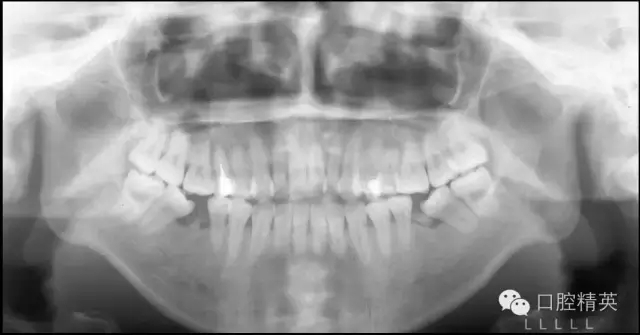

既然我們很難改變患者髁突生長(zhǎng)不足的問題,就只好從控制其上頜骨及磨牙區(qū)的垂直生長(zhǎng)著手了,由于抑制生長(zhǎng)本非易事,控制患者的磨牙高度就成了控制其下頜平面最切實(shí)可行的手段。而通過壓低磨牙來控制高角患者的下頜平面,乃至實(shí)現(xiàn)其下頜平面的前上旋轉(zhuǎn)正是后部垂直向控制的概念及意義所在(圖1)。

圖1 通過壓低磨牙進(jìn)行后部垂直向控制